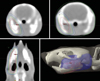

Fig. 2

Coronal fat-suppressed T2-weighted MR image. In order to locate the same plane every week, the axial (pulp floor of molar teeth), sagittal (midline of face), and coronal (first molar including two roots) planes were adjusted. The location of the region of interest (ROI) was used to measure the signal intensity in the mandibular first molar area. The ROIs included the alveolar bone marrow between the first molar and the incisor, and the adjacent muscles.

Fig. 3

The ROI of the incisor pulp tissue below the molar teeth on the modified sagittal section is obtained along the long axis of the incisor.